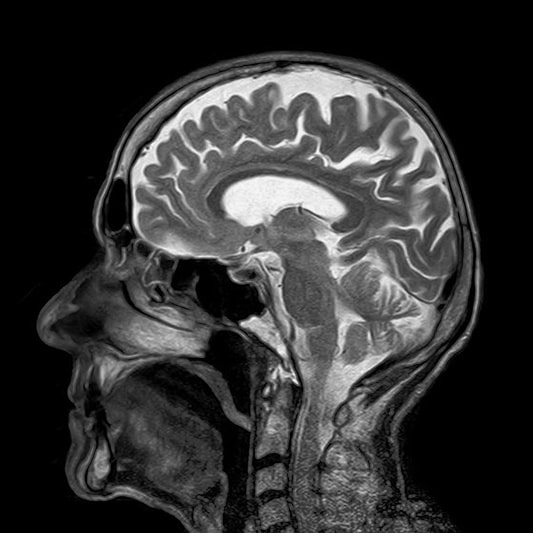

2. 영상 검사

파킨슨병 진단 시 가장 중요한 MRI 검사입니다.

MRI 검사를 통해 파킨슨병인지 아니면 뇌병변으로 인한 증상인지를 판별합니다.